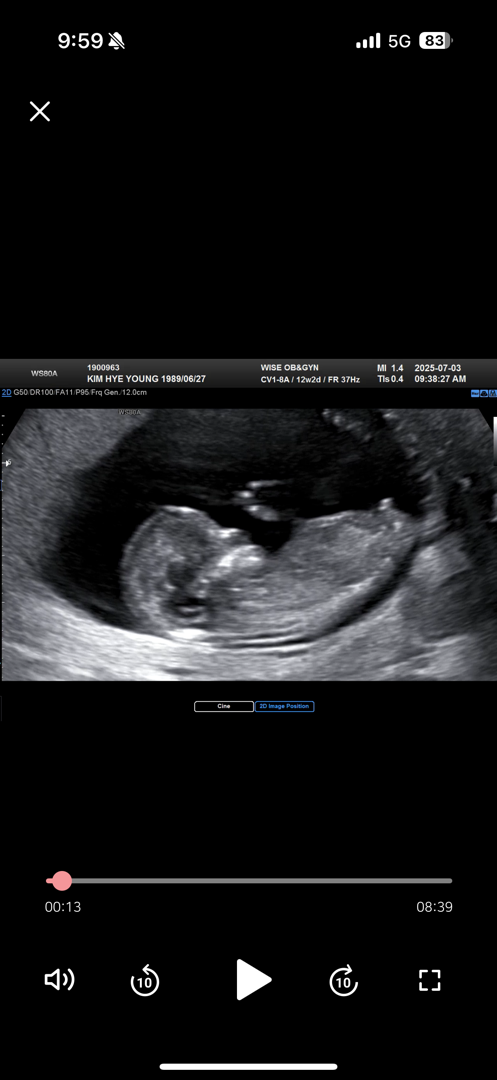

12주각도법 !!참견해주세요!

다들 어떻게 보시나용?? 위로 솟은거 같기도....ㅠㅠㅠ